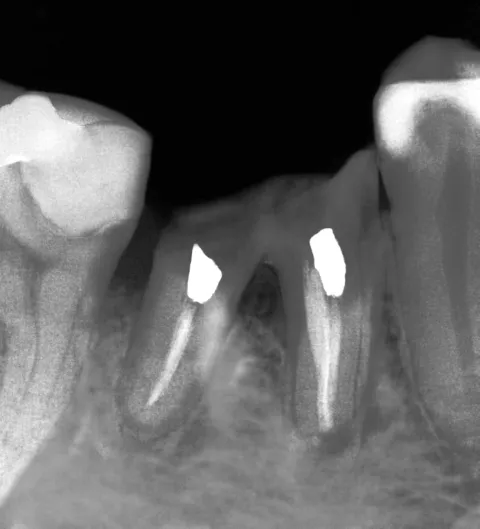

FLUJO DE TRABAJO PARA LA COLOCACIÓN INMEDIATA DE IMPLANTES EN ALVÉOLOS POSTEXTRACCIÓN

1. Lugar de extracción molar

2. Alvéolo de extracción con varias raíces

3. Colocación inmediata de implante con

Helix GM™ 6,0 mm